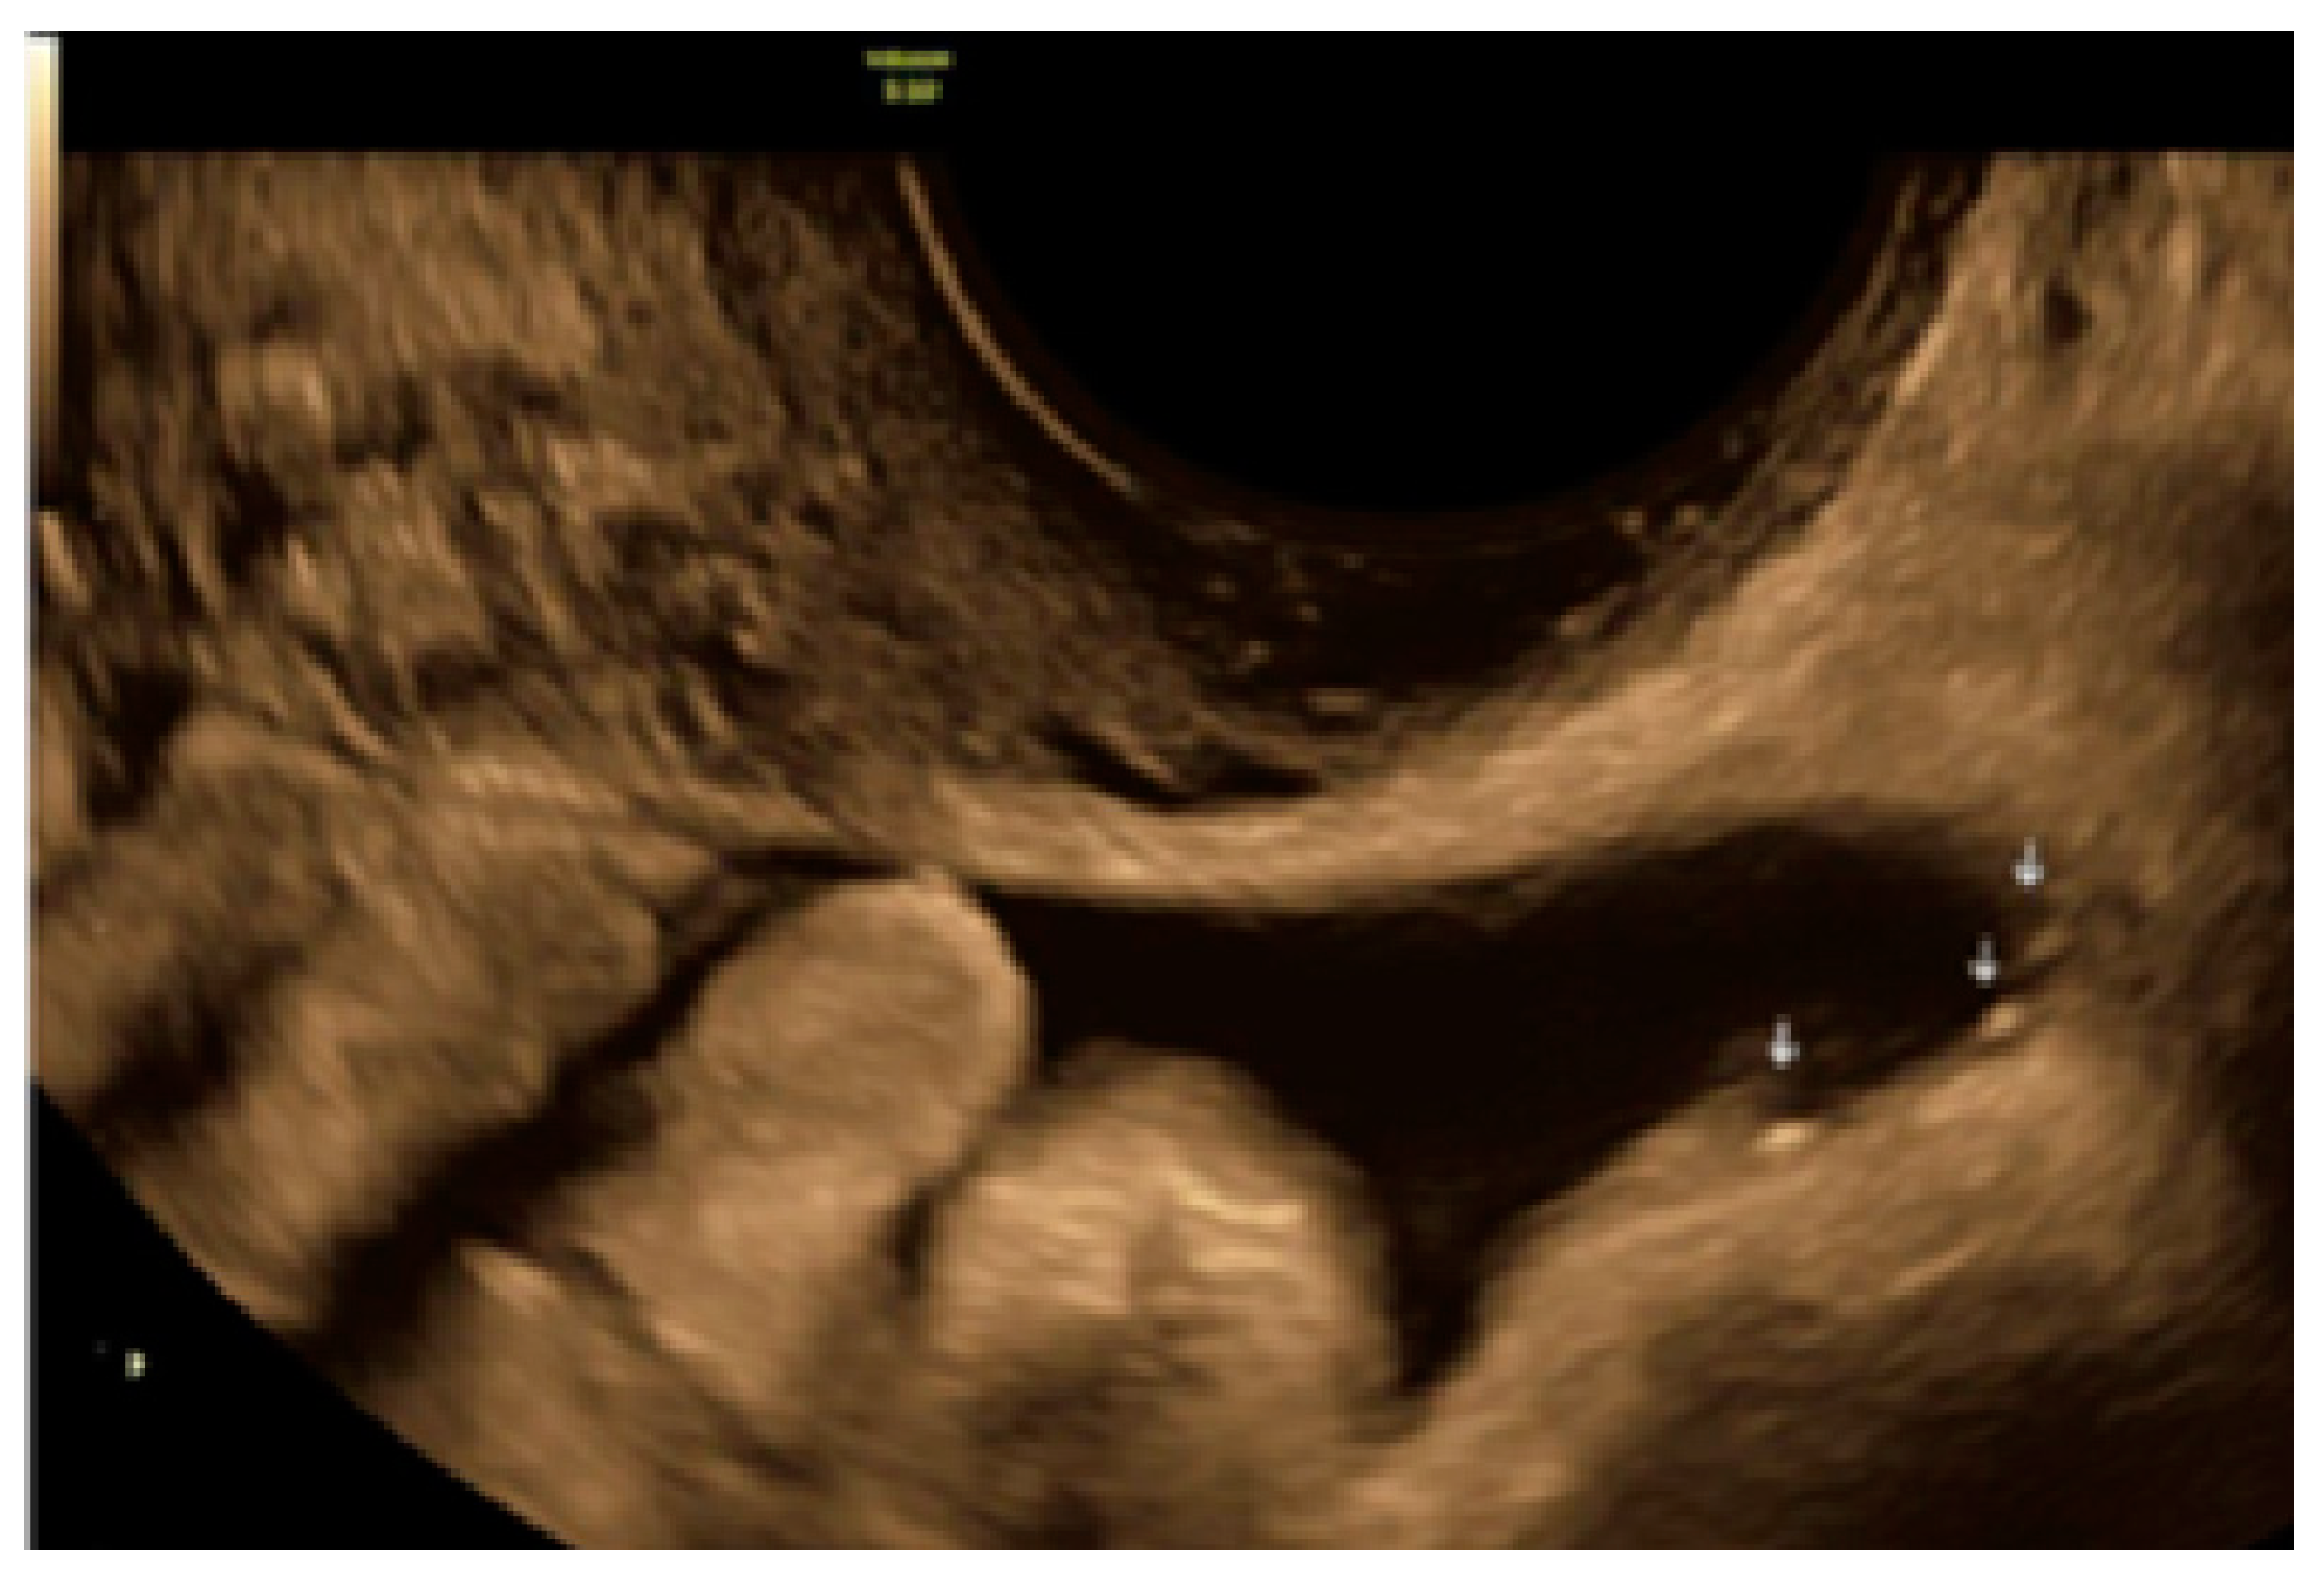

3.3. Cystic Lesions Arranged in a Cluster

- The lesion may be convex, protruding from the peritoneal surface into the peritoneal cavity (we called this “bulging”), or it may appear as a concave defect in the peritoneum (we called this a “pocket”).

- The presence of hypoechogenic associated tissue (hypoechoic areas surrounding a small cyst area; we called this a “hat”). This tissue does not protrude or invaginate the peritoneal surface.